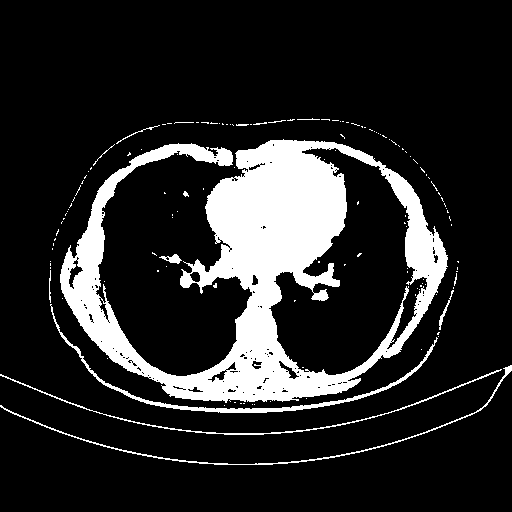

Original NATIVE CT scan (input)

Full window (WL 1023.5, WW 4095 β†’ Low βˆ’1024, High +3071)

Actual HU range: [-1024.0, 3071.0]